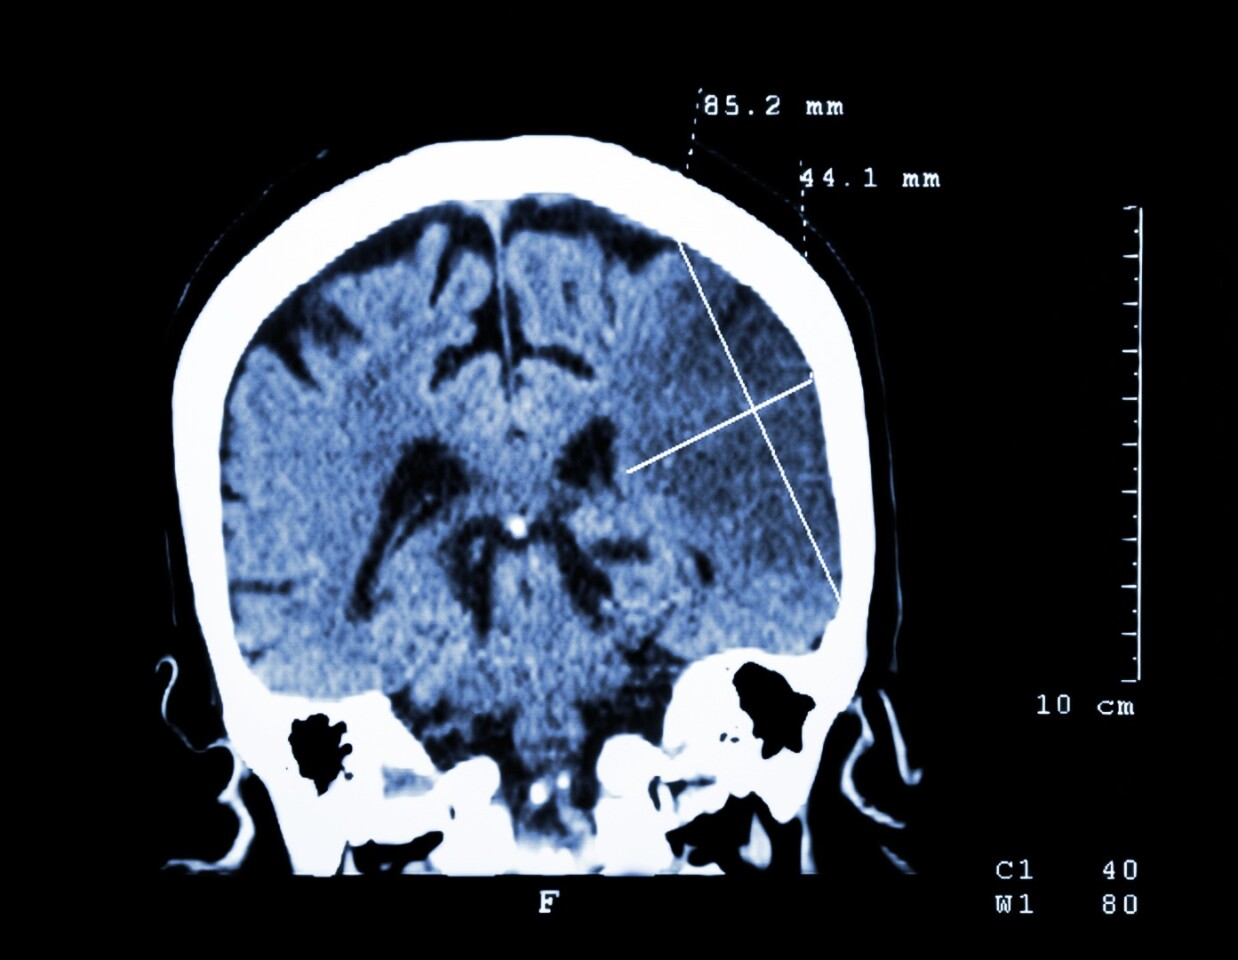

According to the American Stroke Association, stroke is the fifth leading cause of death in the US and one of the leading causes of adult disability. The death of brain cells due to lack of oxygen can result in, amongst other things, problems speaking, understanding speech and paralysis. Rehabilitation is a long, often lifetime, process, but researchers have found that a drug already used to treat certain conditions in humans can not only limit the effects of stroke, but also help repair the damage caused.

In a study involving rodents suffering stroke, researchers at the University of Manchester discovered that anti-inflammatory drug, interleukin-1 receptor antagonist (IL-1Ra), which is already approved for use in humans for the treatment of rheumatoid arthritis, limits the death of existing brain cells as well as promoting the birth of new neurons. The team found that there was a reduction in brain damage in rodents treated with IL-1Ra in the early stages after a stroke, while increased numbers of new neurons were found several days after the treatment.

While stem cell treatments have shown promise in studies for patients suffering the effects of a stroke, attempts to uncover drugs that can prevent initial brain damage after stroke have proven unsuccessful. So the fact IL-1Ra also appears to help the brain repair itself by generating new brain cells, with rodents regaining motor skills that were initially lost after stroke, is obvious cause for hope.